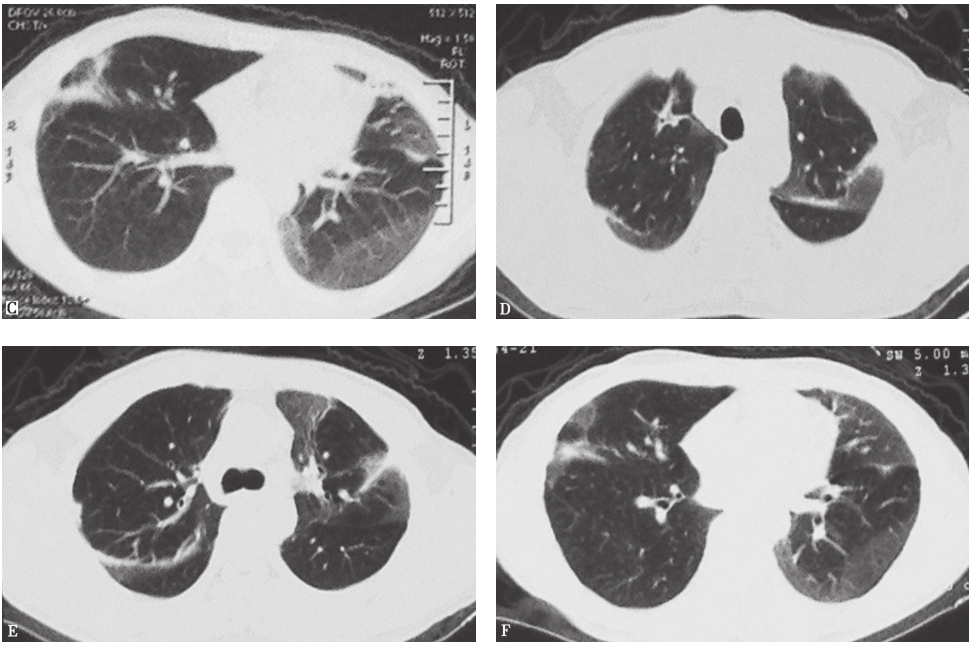

随访结果:醋酸泼尼松40mg(每天1次)并予护胃、补钙等治疗3天后,患者干咳症状明显好转,未诉其他不适。继续口服激素治疗2个月后复查胸部CT,显示病变明显好转(图4)。

图4激素治疗后胸部影像学变化

A~C.2013年1月30日(泼尼松40mg治疗2周后)胸部CT显示肺部病变较前明显好转;D~F.2013年2月20日(泼尼松治疗6周后)胸部CT提示肺部病变较前进一步好转